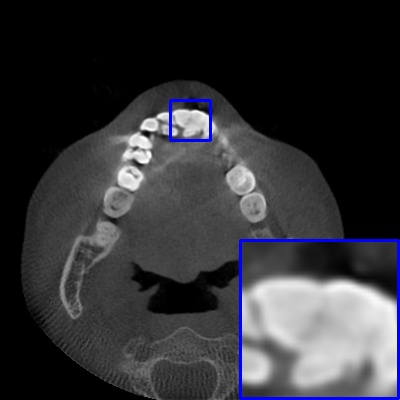

Figure 3: Visual comparison of MAR images by different methods on synthetic MA image. The PSNR (dB)/SSIM results are reported below each image for reference.

Results on synthetic MAR. In Table 1, we provide the quantitative results. One can see that our MARformer-L outperforms the other methods in terms of PSNR and SSIM, but needs only 11.76M parameters and 60.25G FLOPs. Note that the second best method Uformer-B has 50.42M parameters and 205.82G FLOPs. Besides, our MARformer-T achieves similar PSNR and SSIM results with Uformer-T, but needs only 0.40M parameters and 12.82G FLOPs compared to 5.24M and 25.39G for Uformer-T. Our MARformers also achieves faster inference speeds than the Uformers, though with inferior Dice scores, respectively. The qualitative results of visual quality are presented in Fig. 3. We observe that our MARformer-L well recovers the teeth shapes and obtains higher PSNR and SSIM results than the other comparison methods. The light-weight MARformer-L achieves similar results to Uformer-T. All these results validate that our MARformer is more efficient than the comparison methods on dental CBCT MAR.